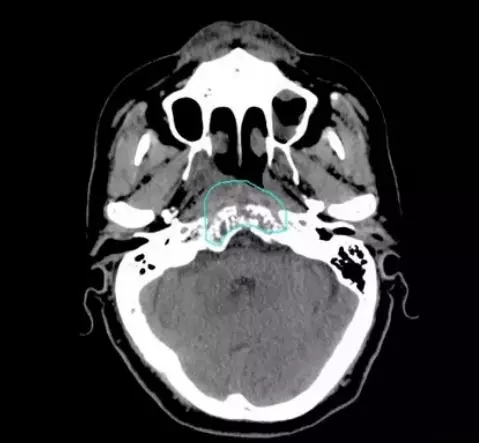

治疗1个月后复查,肿瘤明显缩小,无不良反应